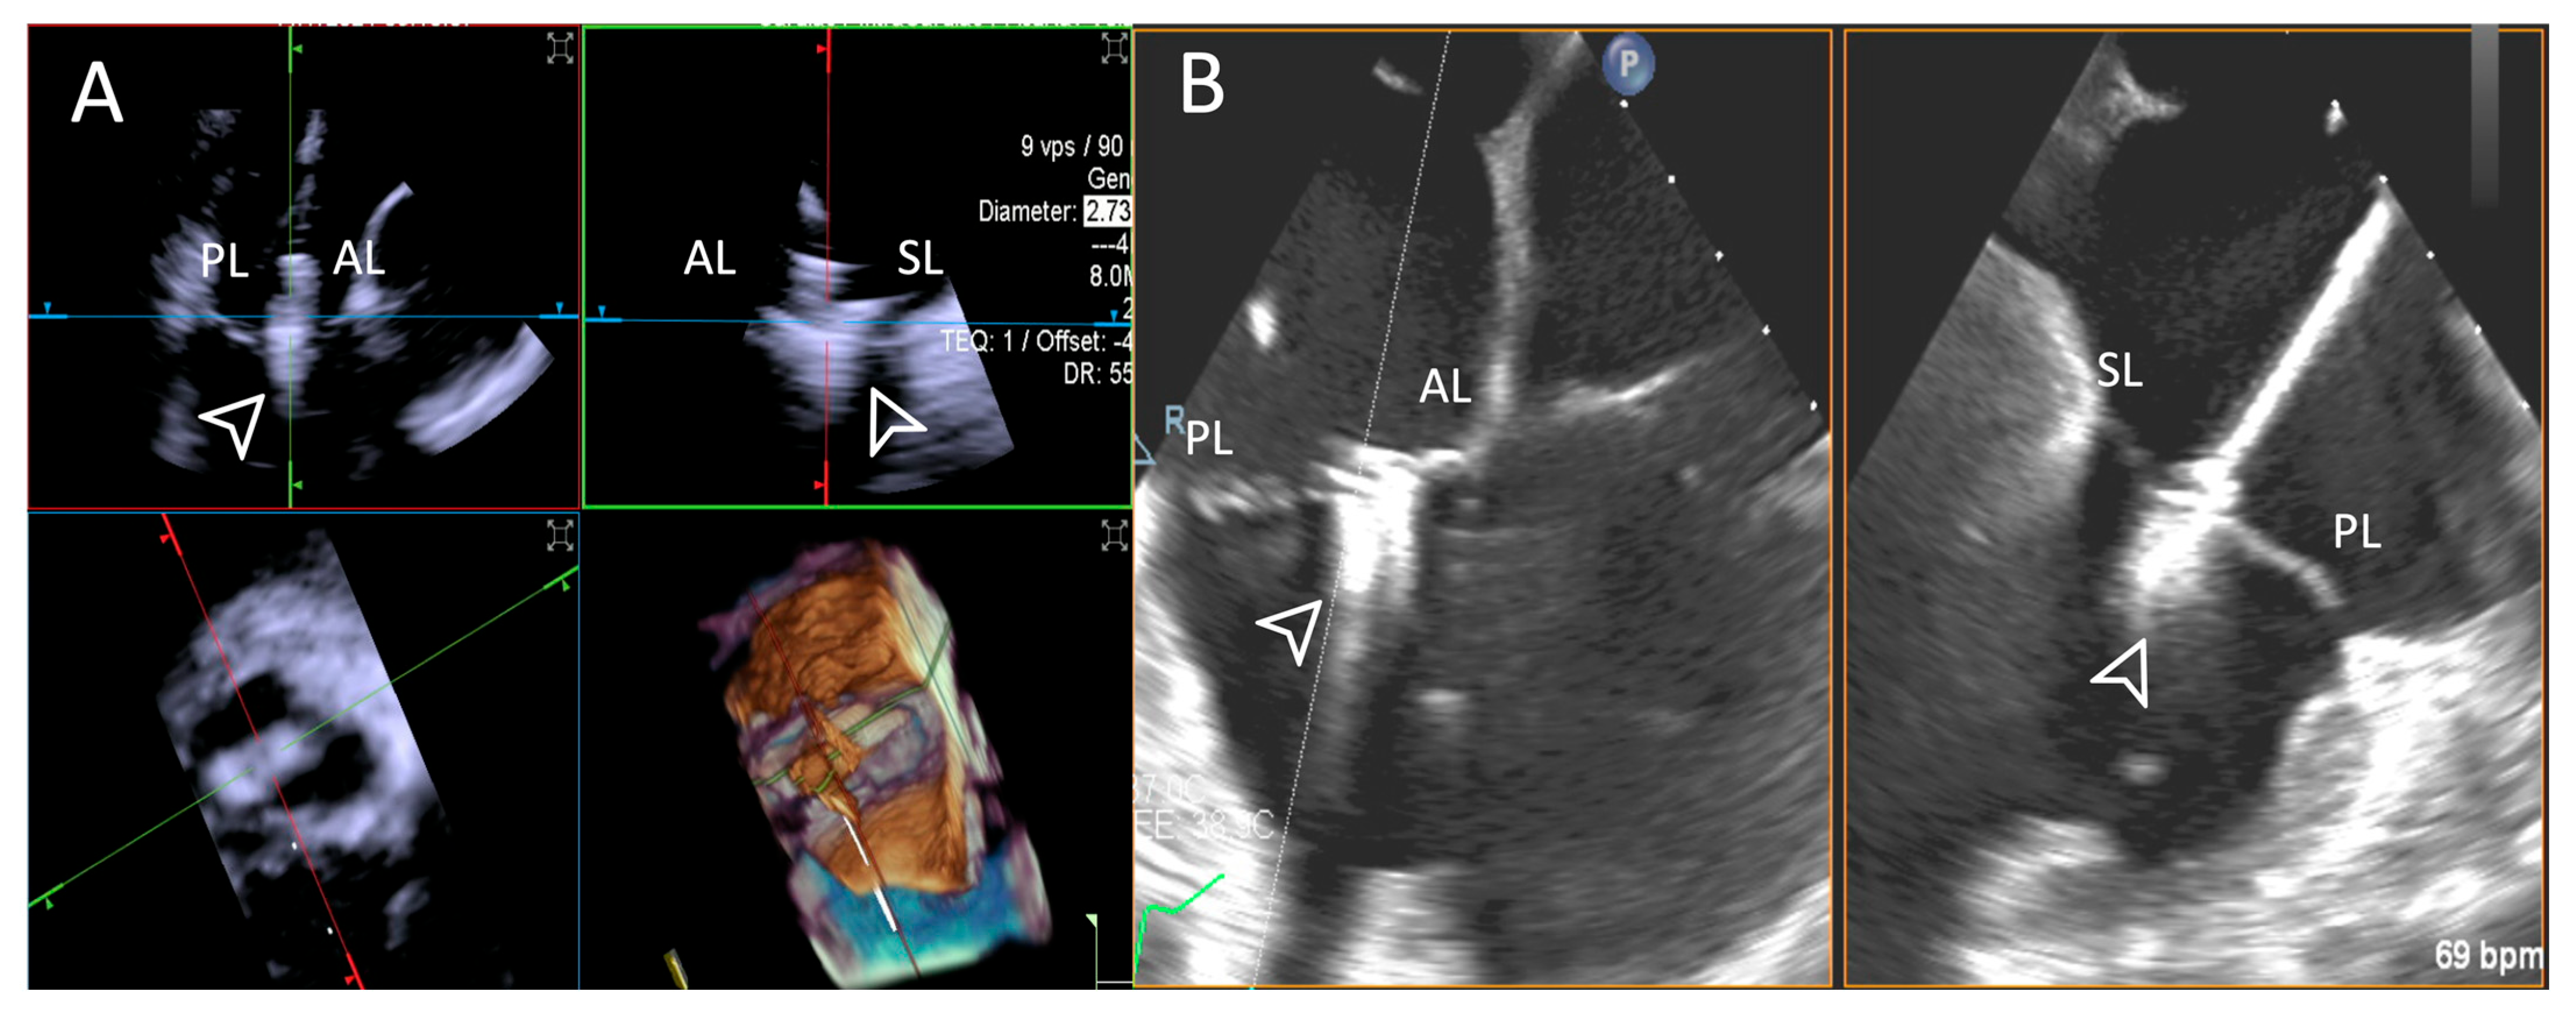

- Step number 1: assessment of tricuspid valve anatomy.

- Step number 2: identification of the target lesion.

3.3.1. Step-by-Step Evaluation

3.3.2. Quantitative Measurements Comparison